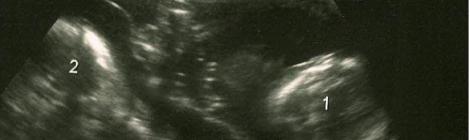

Apprendre que l’on porte des jumeaux peut créer toutes sortes d’émotions positives ou négatives. Pour ma part quand j’ai su que j’attendais des jumeaux comme première grossesse, j’étais super contente […]